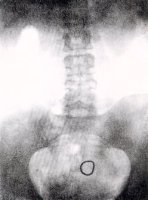

De izquierda a derecha. Arriba: Dispositivo para la inserción del anillo de Gräfenberg. Tres muestras del anillo.Posición del anillo insertado mostrado por rayos X.